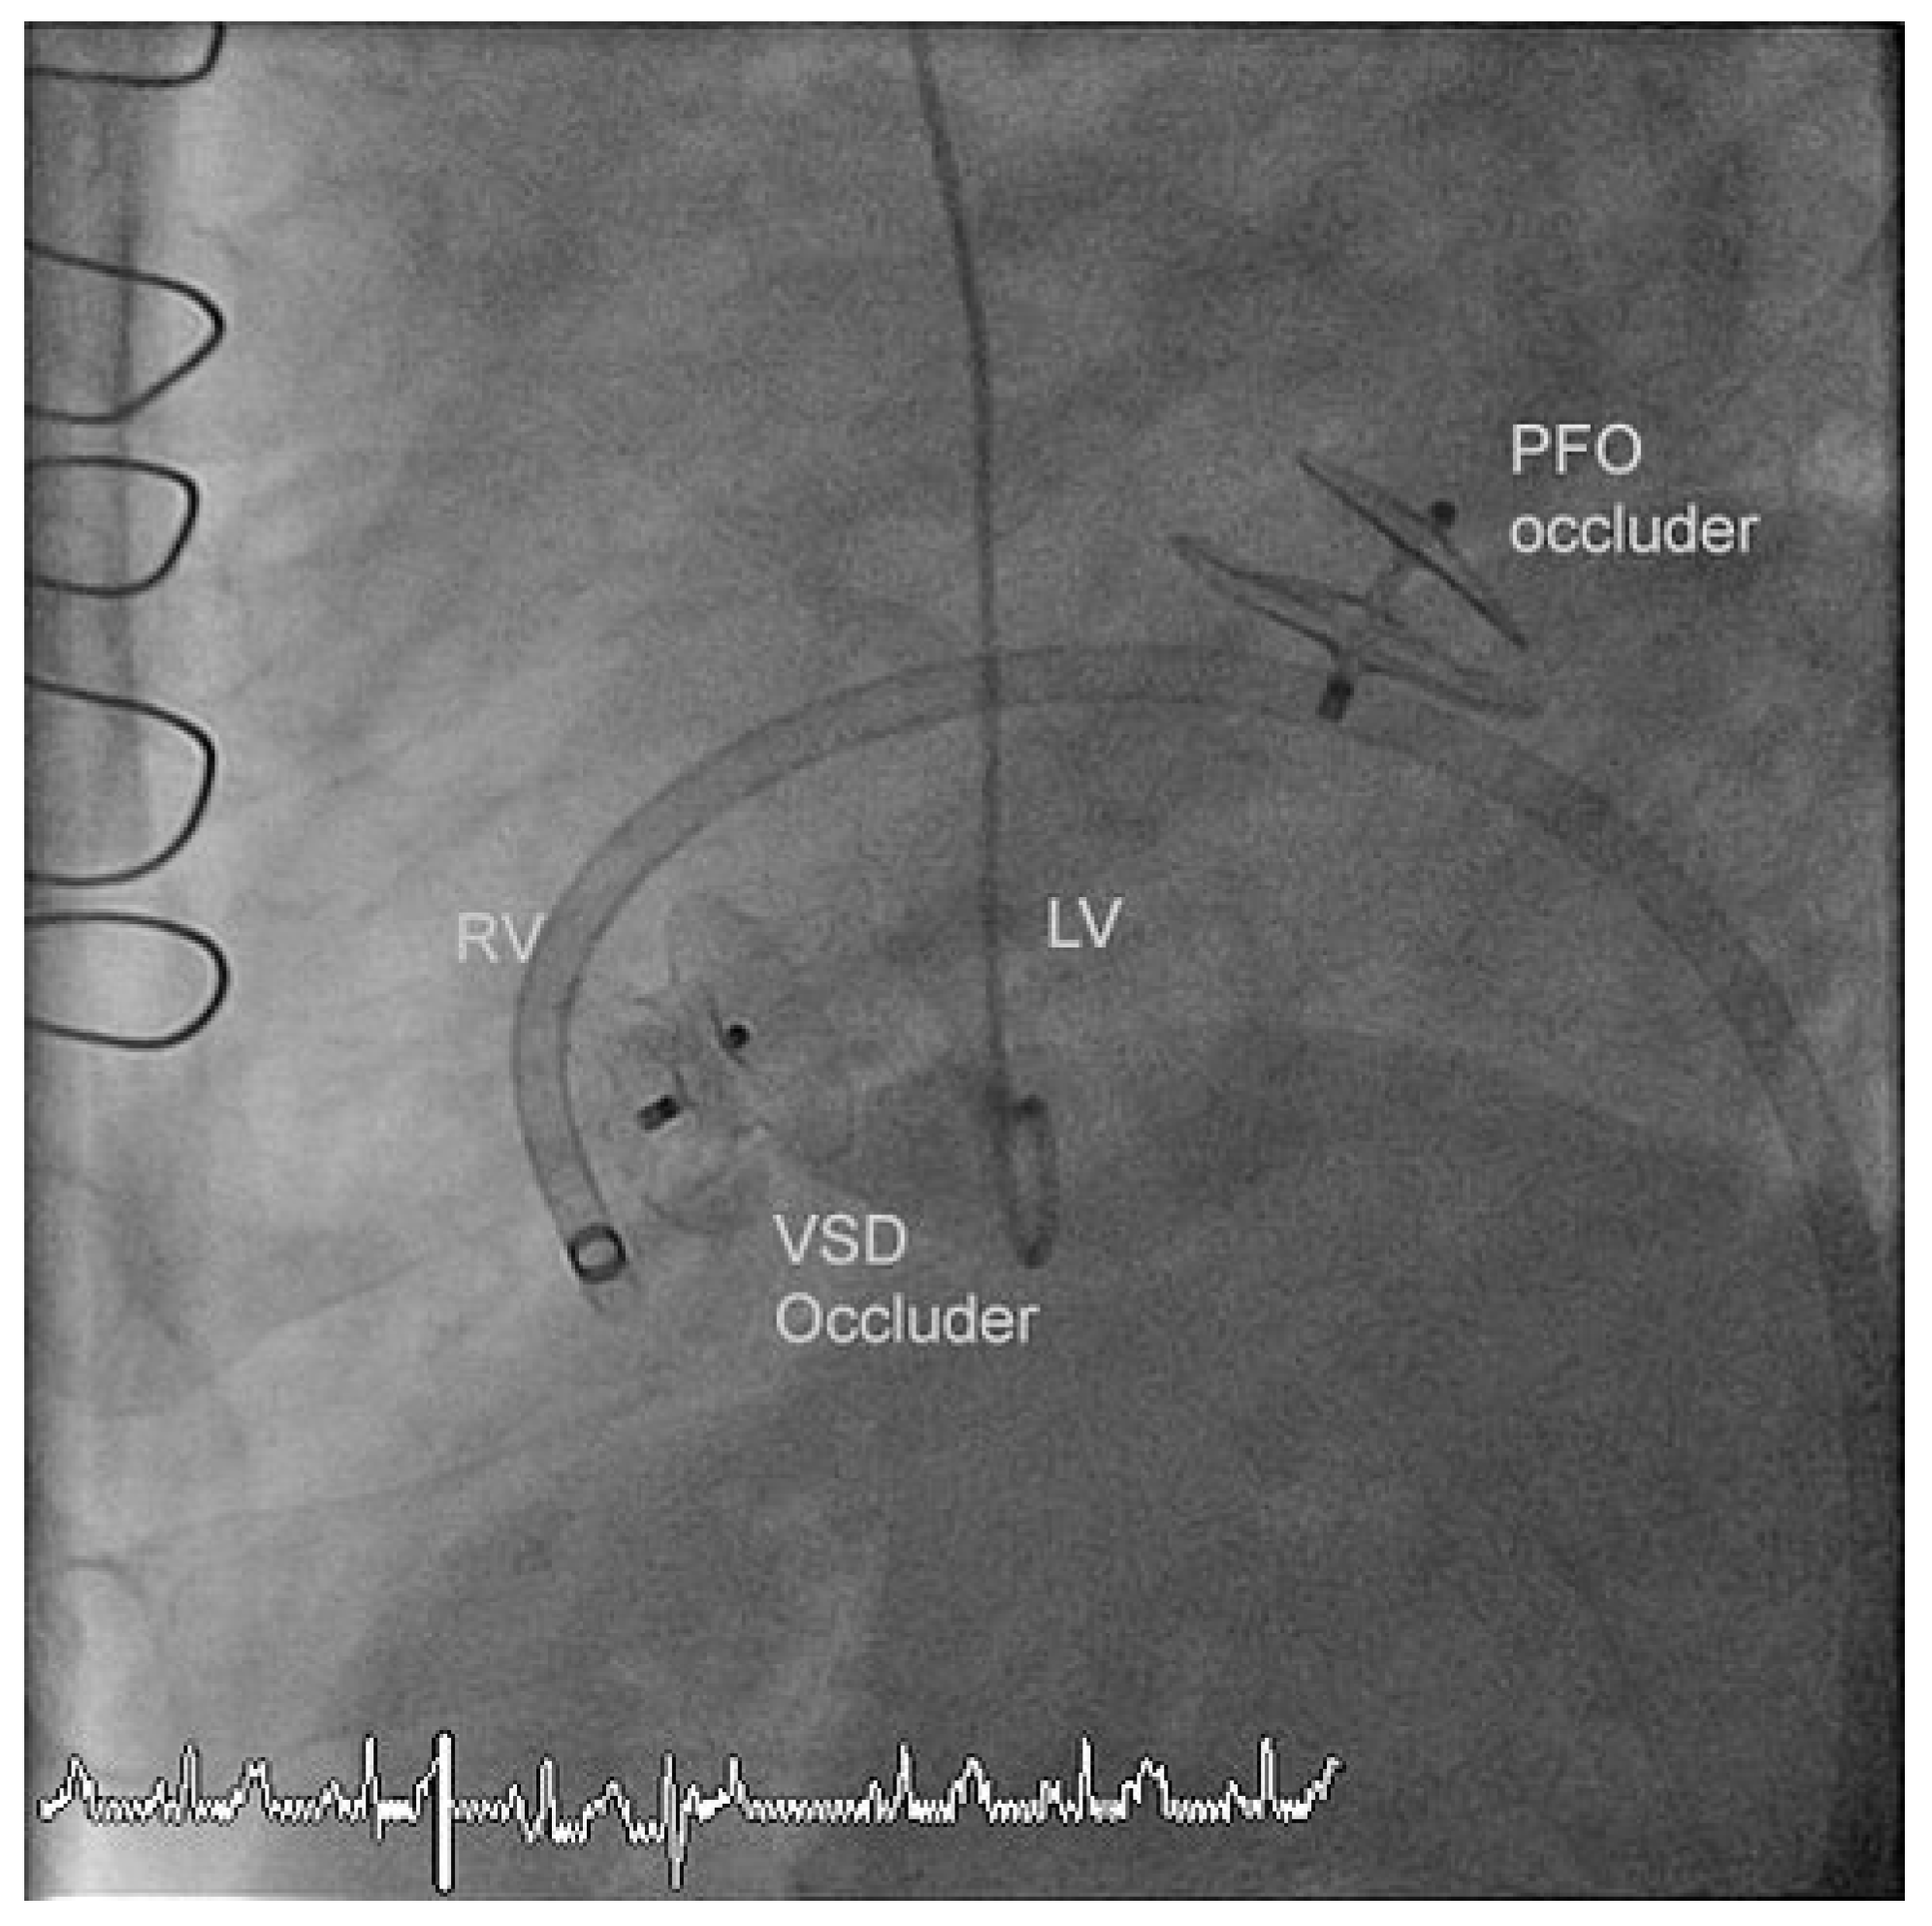

The residual VSD was identified with left ventricular contrast injection and the defect was crossed from the left ventricular side using a guide wire which was snared in the pulmonary artery and exteriorized thus creating an arteriovenous loop. The VSD was measured using a 34 mm sizing balloon (St. Jude-AGA) (Figure 1). A 14 mm Amplatzer muscular VSD occluder (St. Jude-AGA) was implanted through an 8 F TorqVue sheath (St. Jude-AGA) inserted through the right femoral vein (Figure 2). Adequate position was confirmed under fluoroscopy with contrast injection into the left ventricle (Figure 3). The procedure was performed without TEE and under local anaesthesia.

At the same time coronary angiography detected a total (re-)occlusion of the posterior descending and the posterolateral branch of the right coronary artery and a significant stenosis of the distal right coronary artery which were treated with balloon angioplasty. The PFO Amplatzer Occluder implanted seven years earlier was free of residual shunt.

Figure 2. Insertion of the Amplatzer muscular VSD occluder (14 mm) from the right ventricle.

Figure 3. Adequate position of the VSD occluder with minimal residual shunt in the old PFO Occluder.